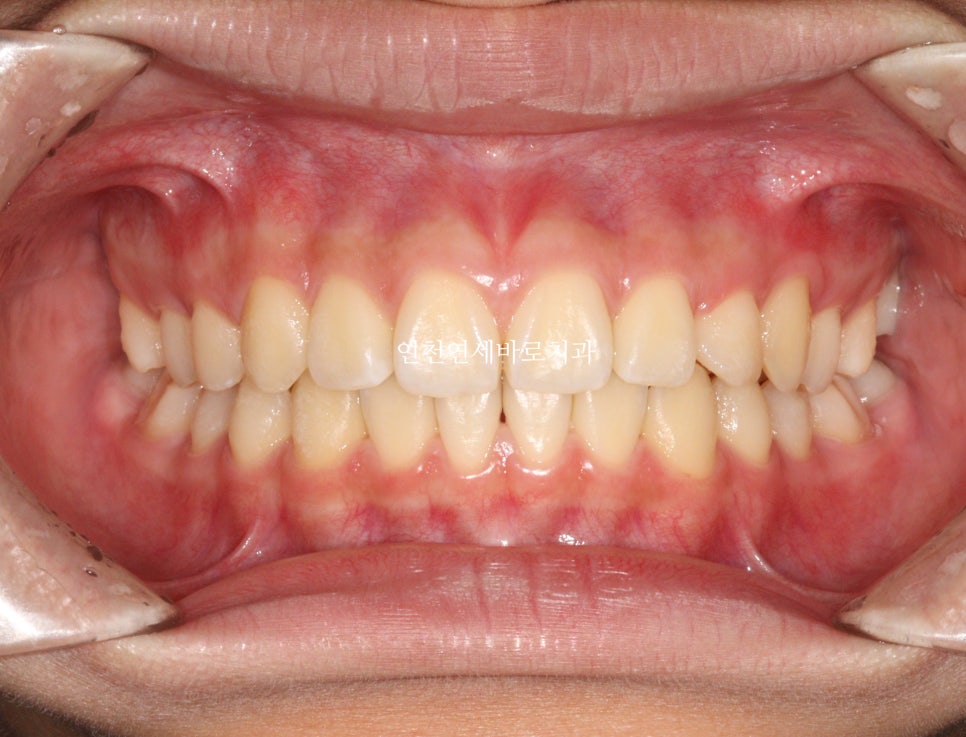

사진상 2 1 3 이라고 표시된 치아의 원래 순서는 1 2 3 입니다.

어느정도라면 원래의 순서로 배열하기도 하지만, 이 친구는 2 1 3 순서로 배열하기로 했어요.

중심선도 잘 맞고

교합도 양호합니다.